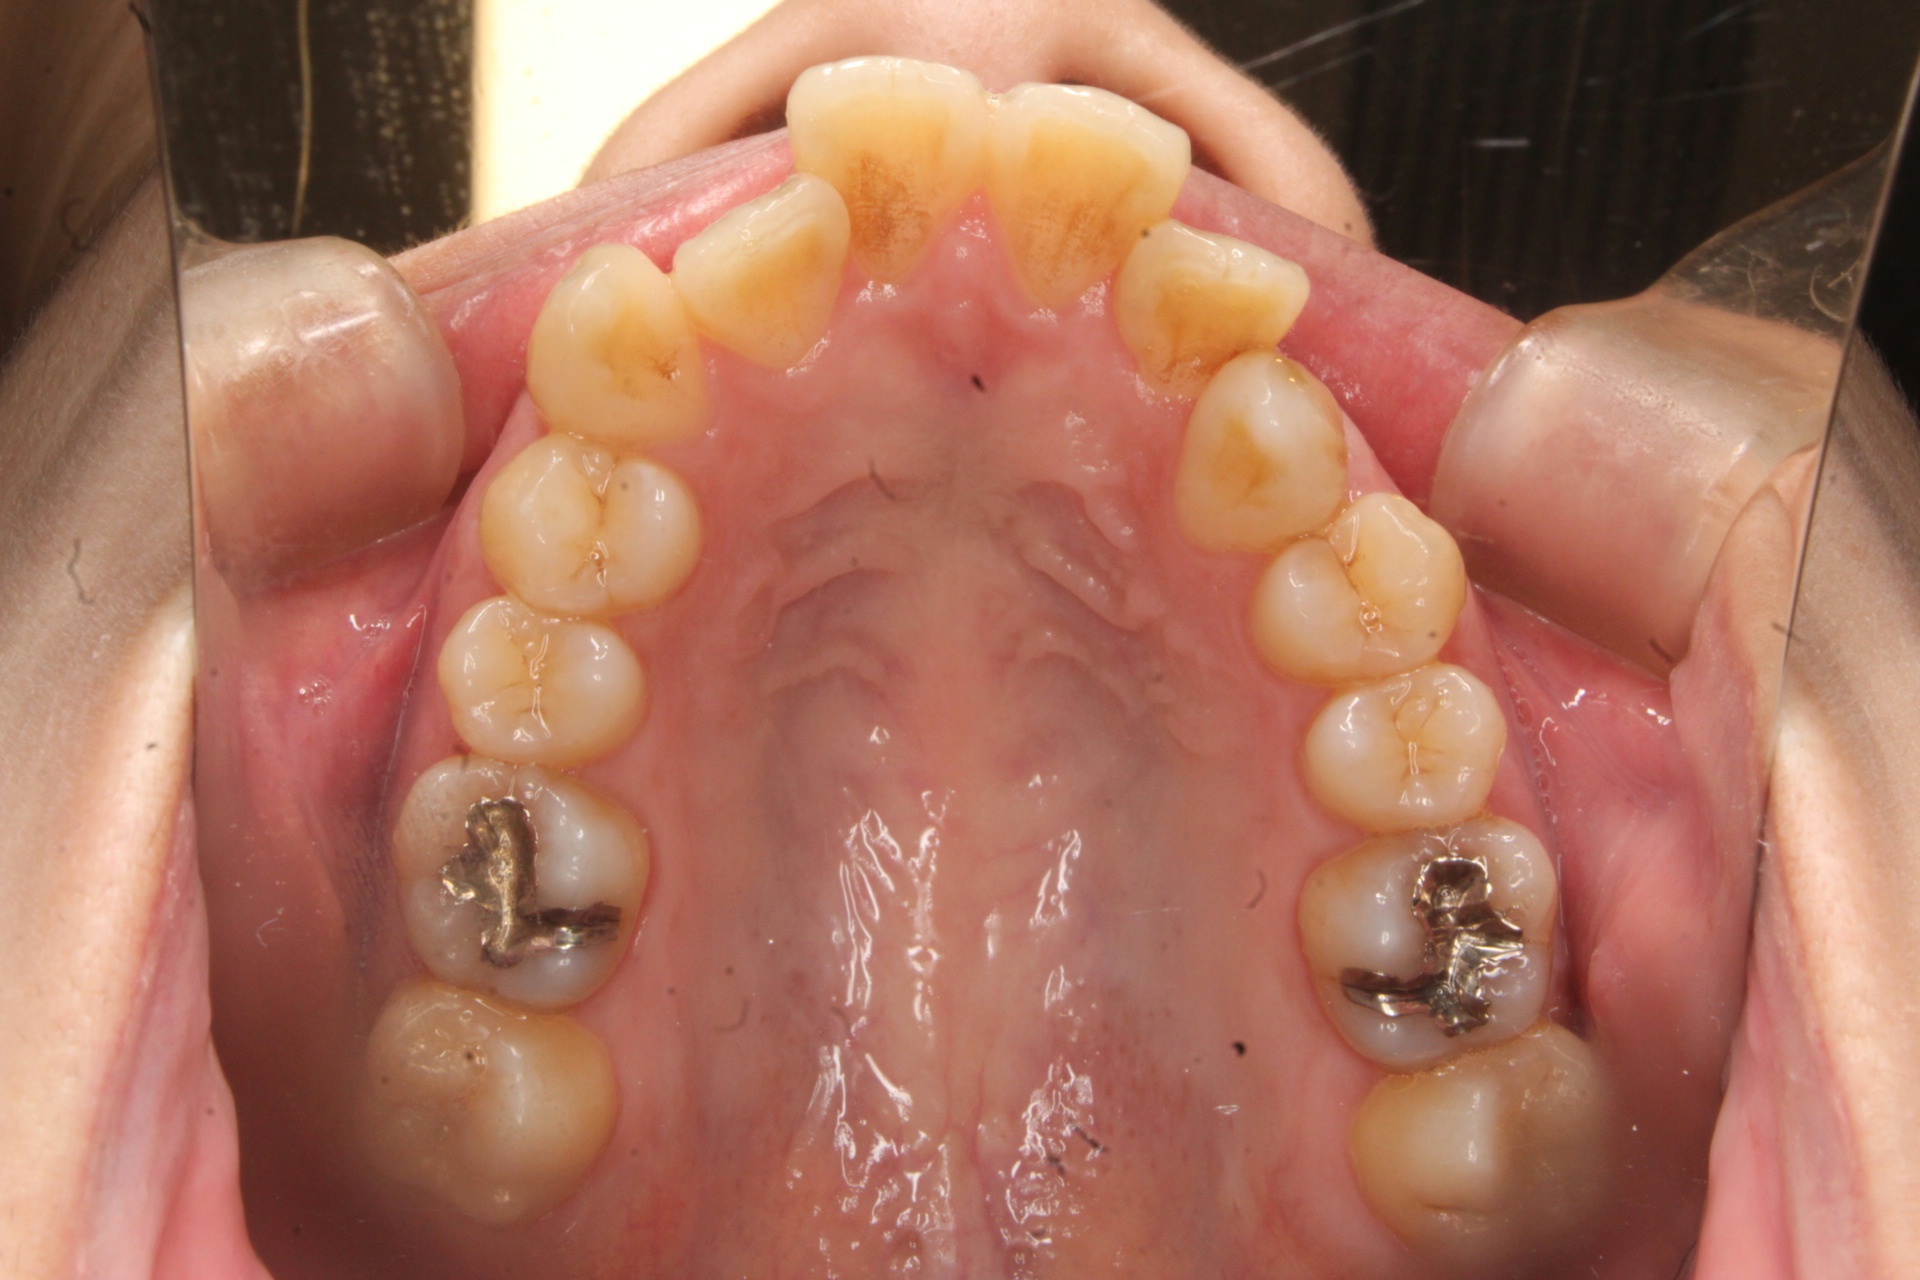

主訴 【主訴】出っ歯を治したい 【診断・症状】上下凸凹、口元が出てる

治療費用 検査・診断:38,500-/裏側矯正治療:1,397,000-(※全て税込)

治療期間 約2年9か月(36回)

抜歯 抜歯:有(上4,4)

矯正の装置 裏側矯正(舌側矯正)

副作用、リスク 歯肉退縮,歯根吸収,疼痛,咬合の違和感,装置の違和感,虫歯,歯肉炎